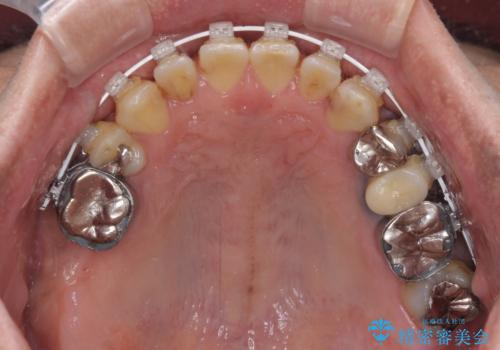

来院当初は、奥歯の銀歯が問題で咬み合わせが悪いと思っていらっしゃいましたが、前歯の反対咬合を改善することが最優先とご説明し、矯正治療を行うこととしました。

奥歯には抜歯が必要な歯があったため、事前に抜歯を行い、その後ワイヤー装置にて治療を開始しました。